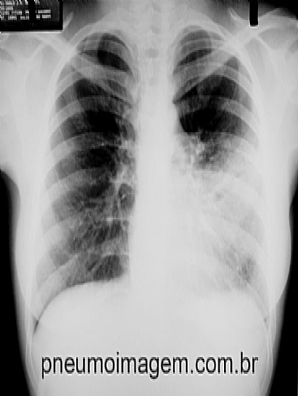

Veja imagens de pneumonia de acordo com o patógeno ou a localização anatômica no PneumoImagem

clicando aqui.